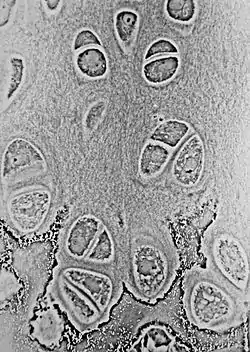

![]() Zona hipertrófica da placa epifisária apresentando três zonas: de maturação (parte superior), degenerativa (parte média) e de calcificação (parte inferior). | |

A placa epifisária apresenta uma morfologia muito específica com um arranjo em zonas.[1]

| Zona da placa epifisária (da epífise para a diáfise) | Descrição |

|---|---|

| Zona de reserva | São encontrados condrócitos quiescentes na região terminal da epífise. |

| Zona de proliferação | Os condrócitos realizam várias mitoses sob a influência do hormônio do crescimento. |

| Zona de maturação e hipertrofia | Os condrócitos interrompem as mitoses e começam a sofrer hipertrofia devido ao acúmulo de glicogênio, lipídios e fosfatase alcalina. |

| Zona de calcificação | Os condrócitos sofrem apoptose. A matriz cartilaginosa começa a ser calcificada. |

| Zona de ossificação | Os osteoclastos e os osteoblastos da diáfise penetram na cartilagem calcificada e a substituem por tecido ósseo mineralizado. |